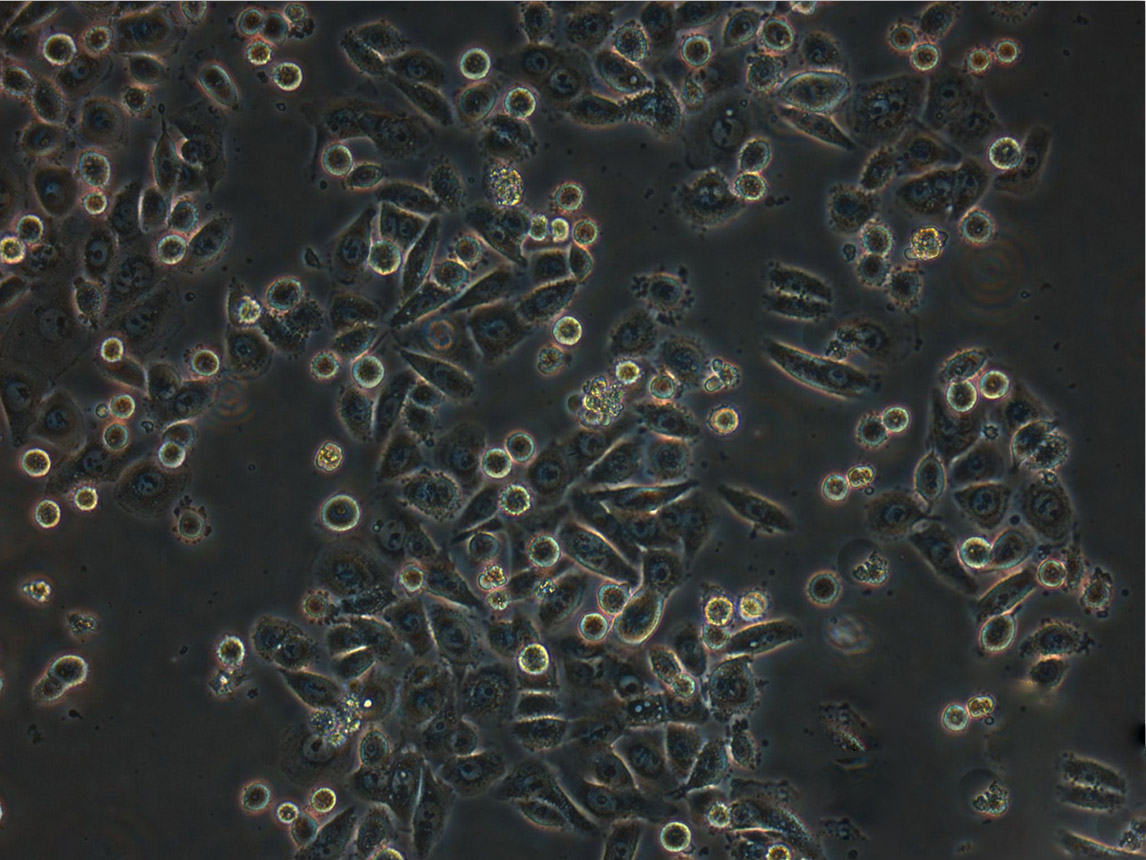

细胞形态:上皮细胞样

细胞生长:贴壁

细胞生长特性:贴壁生长